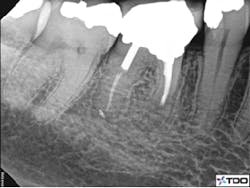

Figure 2 demonstrates a case with failing endodontic therapy. The mesial canals show inadequate obturation, and a periradicular radiolucent area is apparent. The tooth was retreated, and figure 3 shows the one-year follow-up. Note the resolution of the radiolucency. This case demonstrates the concept of removing the etiology of the bacteria with nonsurgical treatment.